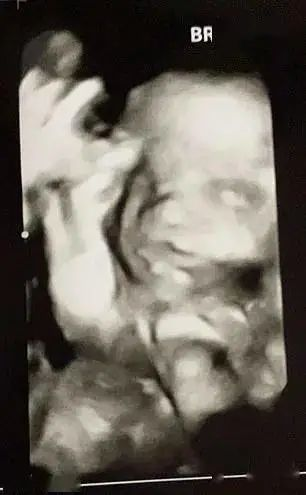

分享在社交媒体的假孕肚照、伪超声波照片